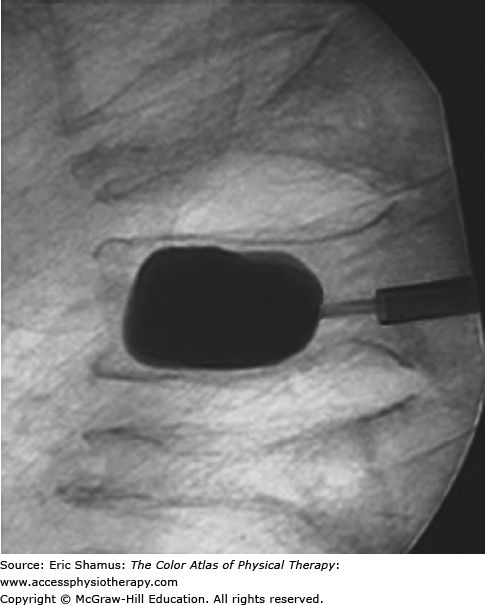

Scenario: The patient is a 72-year-old woman who is having mid-thoracic pain after a coughing bout. The patient is having a dull ache pain that is constant. Upon X-rays, thoracic compression fractures are found. The patient received kyphoplasty surgery. Physical therapy treatment followed by progressive weight-bearing exercises.